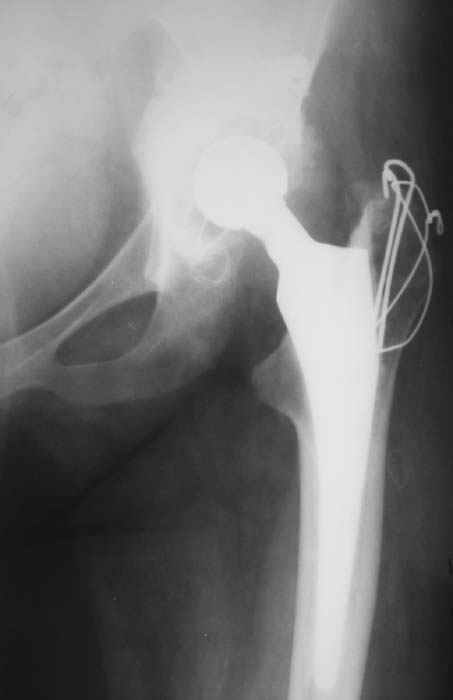

Уважаемые коллеги! Женщина, 28 лет. Страдает ревматоидным полиартритом, гормонозависима. 6 месяцев назад перенесла тотальное эндопротезирование левого тазобедренного сустава по поводу протрузионного коксита.

Использована цементная версия с пластикой дна впадины измельченной аутокостью и гранулами гидроксиапатита. Субъективное улучшение после операции. Улучшилось и стабилизировалось общее состояние. В настоящее время затруднено передвижение из-за поражения правого коленного сустава. Болезненный и <болтающийся> сустав. Предполагается замена сустава протезом без сохранения задней крестообразной связки. Возможные варианты? Заранее благодарю! С уважением,А.В.ВладзимирскийДонецкий НИИ травматологии и ортопедииДонецк, Украина

Без вариантов. Зря цемент в т\б сустав, но это прошлое. А Рыков Хабаровск.

Все правильно, но я бы применил бесцементный протез. Это мнение совпадает с мнением хирургов из НИИ ревматологии. Делайте колено. АИФ.

Пациентке всего 28 лет очень рано тотальное цементное ендопротезирование.Жизнь цементной версии намного короче безцементной